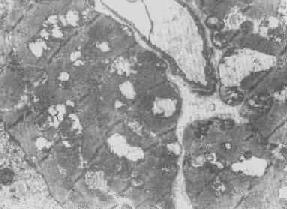

心肌细胞线粒体

图1-8 心肌细胞线粒体